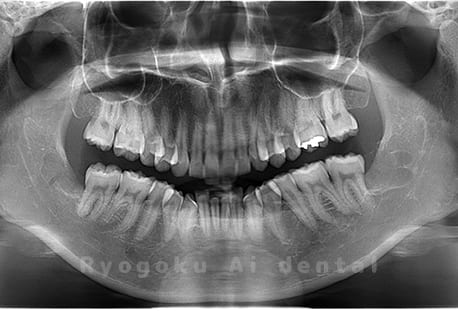

Case02

- 原因

- 下顎の水平埋伏智歯

- 治療内容

- 下顎の水平埋伏智歯を抜歯

<リスク・副作用>

手術後は痛み、腫れ、痺れなどの副作用が生じる場合があります。